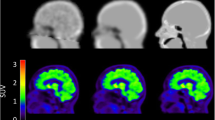

Figure 2 shows axial slices of the last PET frame (65–70 min) at the height of the striatum, occipital pole, and cerebellar cortex of an exemplar subject, reconstructed using μ-mapDXN, μ-mapdUTE, μ-mapdUTE−R2, and pCT, together with the En obtained in each case using the pCT as reference. The highest error was observed in regions of bone and air cavities. In contrast, the error measured in the brain was in general lower, in agreement with previous studies [6, 11].

Axial slices of the last PET frame (65–70 min) from one subject at the height of striatum and occipital pole (top), and cerebellum (bottom) reconstructed using μ-mapDXN (A), μ-mapdUTE (B), μ-mapdUTE−R2 (C), and pCT (D). En between the PET datasets obtained using μ-mapDXN (E), μ-mapdUTE (F), and μ-mapdUTE−R2 (G) with pCT

Figure 4 shows the axial, coronal, and sagittal views of the voxel-wise En map normalised across all subjects, obtained from the PET images reconstructed with each of the μ-maps under evaluation, using pCT as reference. The En maps are overlaid on the brain MRI template used for the normalisation, together with the striatum, cerebellar cortex, and occipital pole masks in MNI space. En < 6% are not shown in the En maps since they are below the test-retest error. The μ-mapDXN shows high En in the entire outer region of the brain, while the μ-mapdUTE shows high En especially in the occipital and frontal regions, and close to the sinus. The μ-mapdUTE−R2 shows En < − 6% in focalized areas in the parietal and frontal regions, similar to μ-mapdUTE but to a lesser extent, and En > 6% close to the sinus. Figure 4 also shows the extension of the non-uniformity across the brain, highlighting the importance of the relative location of a reference region with respect to the region of interest.